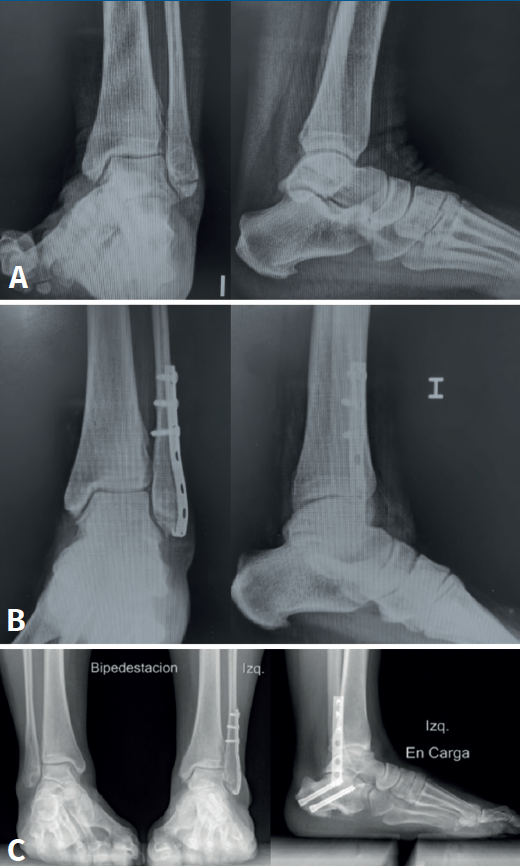

Se trata de una paciente mujer de 54 años con antecedentes de diabetes mellitus de tipo 2 y depresión que presenta una fractura infrasindesmal en contexto de entorsis tratada inicialmente de manera conservadora mediante férula de yeso durante 6 semanas. A los 8 meses presenta persistencia del dolor y se evidencia radiológicamente y con una RM presencia de pseudoartrosis. En este contexto, se decide tratar mediante reducción abierta, fijación interna con placa distal de peroné preconformada y un tornillo de compresión, con colocación de injerto óseo extraído de la cresta ilíaca ipsilateral. En el postoperatorio, la paciente fue inmovilizada con una férula de yeso y a la tercera semana con bota de tipo Walker, manteniendo la descarga hasta las 6 semanas.

A la sexta semana, la paciente no refiere dolor y se objetiva una consolidación de la fractura a nivel radiológico, por lo que se autoriza el inicio de la deambulación sin limitaciones. Al año postoperatorio, la paciente no refería dolor, pero presentaba inestabilidad del tobillo, precisando procedimientos asociados con una plastia de tipo Brostrom y osteotomía del calcáneo de tipo Dwyer en la que también se retiró el tornillo de compresión. Actualmente la paciente está asintomática (Figura 2).